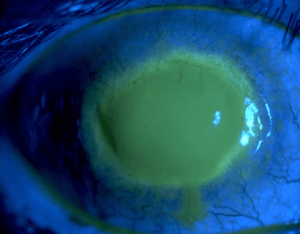

Eye with Acanthamoeba keratitis (fluorescein observation) | |

Acanthamoeba keratitis is a rare disease in which amoebae invade the cornea of the eye. It may result in permanent visual impairment or blindness.[1][2]